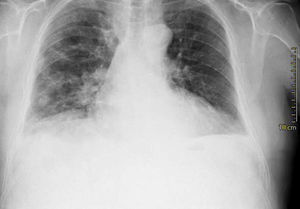

Case presentationIn October 2010 a 74-year-old Caucasian male was admitted because of fever, anuria and mialgia lasting for 2 days. He had no history of renal disease and reported previous normal values of renal function. A month earlier he had travelled to a region of Southern Italy. Physical examination showed normal blood pressure, dyspnoea and jaundice without other dermatological findings; the patient was anuric with 2+pedal oedema. Initial laboratory work-up indicated a total leucocyte (WBC) count of 11,300/μL (neutrophils 88.3%, lymphocytes 11%, eosinophils 0.7%), a haemoglobin level of 9.7g/dL, platelets count of 13,000/μL, serum creatinine 5.25mg/dL, blood urea nitrogen (BUN) 67g/dL, total protein 6.7g/dL, albumin 2.9g/dL, serum sodium 130mEq/L, serum potassium 3.3mEq/L, serum calcium 8.4mg/dL; total cholesterol 254mg/dL; LDL cholesterol 48mg/dL; HDL cholesterol 22mg/dL, procalcitonin 45.71ng/mL, normal value (n.v.)<0.09, Reactive C Protein 22.70mg/dL, n.v.<0.30, ferritin 1300μg/L. Complement C3 and C4, Immunoglobulin G, A and M, kappa and lambda light chains, clotting profile, AST and ALT levels were in the normal range. Total and direct bilirubin values were respectively 4.3 and 2.1mg/dL. Immunological (anti-neutrophil cytoplasm antibodies, anti-nuclear antibodies, anti-double stranded DNA antibodies, anti-extractable nuclear antigen antibodies, anti-phospholipids antibodies, rheumatoid factor) tests were unremarkable. A chest X-ray showed multiple bilateral ground-glass opacities (Fig. 1). A thoracic CT-scan revealed multiple bilateral consolidations and bilateral pleural effusion (Fig. 2). There was to electrocardiogram evidence of normal sinus rhythm and transthoracic echocardiography demonstrated no wall motion abnormality. An abdominal ultrasonography and a CT-scan revealed no abnormalities of liver, gallbladder, kidneys, spleen and pancreas. At the same time of antibiotic, platelet transfusion and diuretic therapy we started continuous venovenous haemofiltration (CVVHF) with weight loss and rapid regression of dyspnoea. Two days after admission the patient showed melena. Subsequent laboratory tests indicated: normal oncologic screening; no signs of haemolytic anaemia; red blood cells and WBC in urinary sediment; a total of 475mg of protein was excreted during a 24-h urine collection; blood cultures examination, tuberculin reaction and HBV, HCV, CMV, EBV, Adenovirus, Chlamydia Pneumoniae and Mycoplasma Pneumoniae screening were negative. During hospitalization we observed a worsening of liver function (total and direct bilirubin respectively 17.30 and 10.50mg/dL, gammaGT 267IU/L, n.v. 7–50, LDH 1027IU/L, n.v. 266–530, AST: 67IU/L, n.v. 10–42, ALT 96IU/L, n.v. 10–45) and inflammation parameters (WBC count 25,250/μL, neutrophils 76.6%, ferritin 4200μg/dL). An abdomen CT-scan highlighted greatly thickened gallbladder and bile duct walls with contrast enhancement, peritoneal effusion and swelling of the visceral adipose tissue (Fig. 3). We performed the Leptospira IgM test (enzyme immunoassay) with positive result. After platelets and erythrocytes transfusions and omeprazole therapy, we started 3g/day ceftazidime and 50mg/day prednisone therapy with a progressive improvement in renal function and general conditions; after 10 days of admission we stopped CVVHF. A thoracic CT scan showed resolution of previously observed lesions. The patient was discharged on day 18. Final laboratory parameters were: creatinine: 0.93mg/dL, BUN: 26mg/dL, total and direct bilirubin respectively 6.50 and 3.40mg/dL, AST: 47IU/L, ALT: 84IU/L, gammaGT: 137IU/L, LDH: 609IU/L, WBC 3420/μL, Hb: 8.3g/dL, and PLT: 262,000/μL.